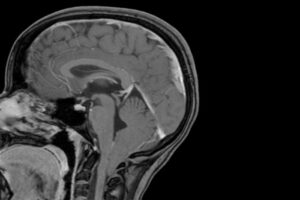

Discovery could aid early screening, shed light on how Chiari malformation arises